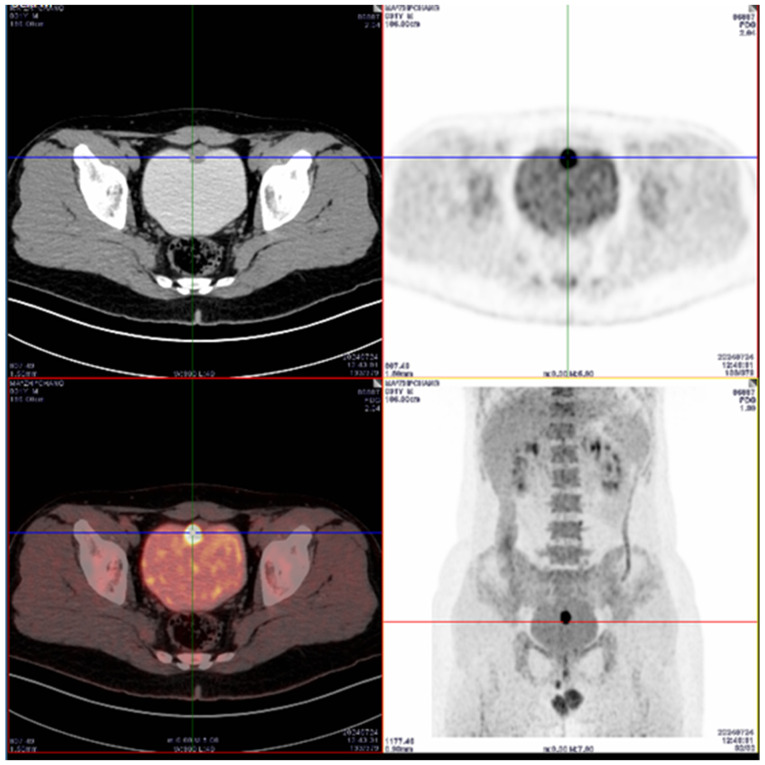

Urachal carcinoma is a rare and aggressive malignancy with an unknown aetiology and poor prognosis. The present case report described a 31-year-old male patient who initially presented with a 5-day history of haematuria. FDG-PET/CT demonstrated nodules in the anterior wall of the bladder with increased glucose metabolism, which were suggestive of malignancy. A cystoscopic biopsy confirmed the diagnosis of urachal carcinoma. The patient underwent en bloc robot-assisted laparoscopic modified partial cystectomy, along the umbilicus and urachus resection, and pelvic lymph node dissection. The patient recovered within 2 weeks postoperatively, with complete tumour resection confirmed by pathological analysis, which showed negative margins and no recurrence was detected during a 5-month follow-up. The current case highlighted the potential of robot-assisted laparoscopic surgery as an effective treatment option for urachal carcinoma, offering insights for further optimization and broader clinical application, and reviewed the currently available literature.

尿管癌是一种罕见的侵袭性恶性肿瘤,病因不明,预后差。本病例报告描述了一名31岁男性患者,最初表现为5天血尿史。FDG-PET/CT显示膀胱前壁结节伴糖代谢增高,提示恶性肿瘤。膀胱镜活检确诊为尿管癌。患者接受了整体机器人辅助腹腔镜改良部分膀胱切除术,沿脐和脐切除,以及盆腔淋巴结清扫。患者术后2周内康复,病理证实肿瘤完全切除,5个月随访,切缘阴性,无复发。本病例强调了机器人辅助腹腔镜手术作为尿管癌有效治疗选择的潜力,为进一步优化和更广泛的临床应用提供了见解,并回顾了现有文献。